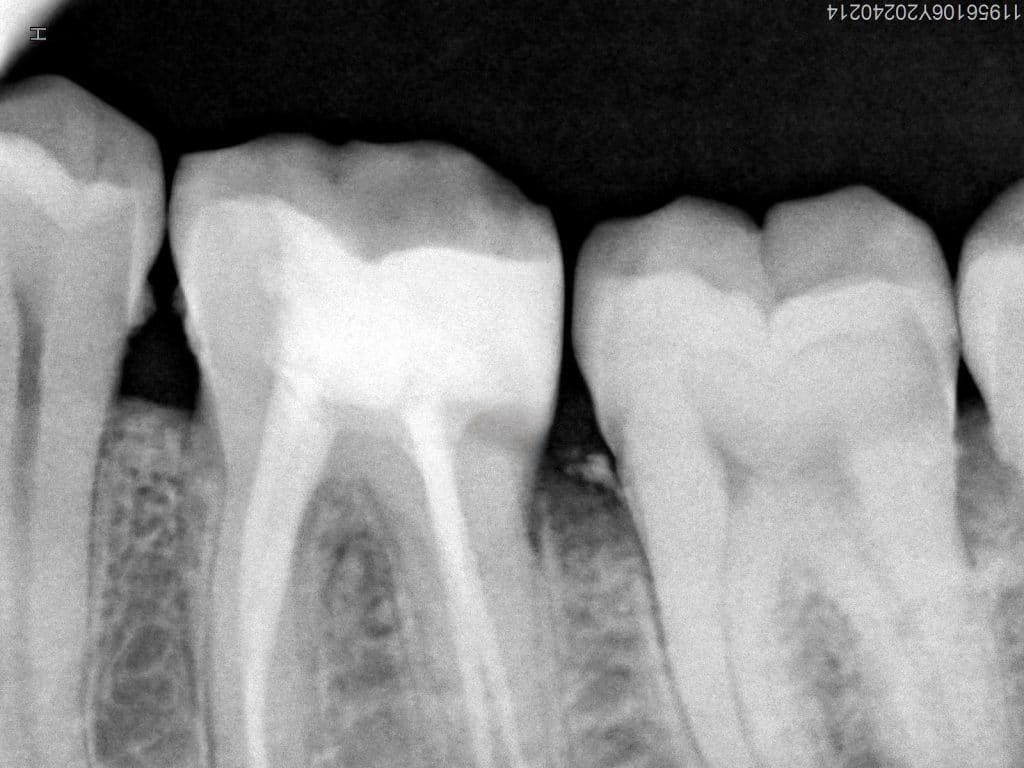

- Case of radix entomolaris of lower left first molar

- The molar had an additional distolingual root(radix entomolaris)

- This root had a severe curvature in its apical third ..it needs patience and time to shape it properly without any mishap

Pre-operative radiograph

Look at the severe curve in the radix